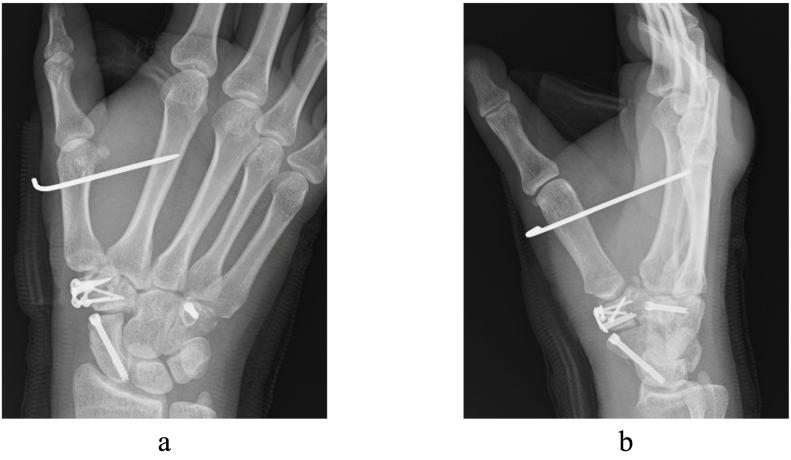

Comminuted trapezium fracture is very rare. As the trapezium is necessary for thumb movements, delayed diagnosis and treatment can result in thumb carpometacarpal (CM) joint osteoarthritis and restricted mobility. The K-wire or screw fixation is recommended for repairing displaced fractures. However, there is currently no established treatment protocol for this rare fracture. In trapezium fracture, a technique with K-wire fixation in addition to open reduction and internal fixation (ORIF) has been reported with favorable clinical outcomes. In this report, we present a case of comminuted trapezium fracture successfully treated with surgery. The present case involved a 26-year-old woman who was injured while driving her car, which led to a comminuted trapezium fracture. ORIF was conducted with headless screws and a locking plate, and the first and second metacarpals were temporarily fixed by K-wire with the thumb in traction. Six months after surgery, bony union and favorable clinical outcomes were achieved. This technique could be beneficial to prevent articular surface collapse in the comminuted trapezium fracture and to achieve favorable clinical outcomes.

粉碎性大多角骨骨折非常罕见。由于大多角骨对于拇指活动至关重要,延迟诊断和治疗会导致拇指腕掌关节骨关节炎和活动受限。对于移位骨折的修复,建议使用克氏针或螺钉固定。然而,目前对于这种罕见骨折尚无既定的治疗方案。在大多角骨骨折中,有报道称一种除切开复位内固定(ORIF)外还采用克氏针固定的技术取得了良好的临床效果。在本报告中,我们展示了一例通过手术成功治疗的粉碎性大多角骨骨折病例。该病例为一名26岁女性,她在驾驶汽车时受伤,导致粉碎性大多角骨骨折。采用无头螺钉和锁定钢板进行切开复位内固定,并在拇指牵引下用克氏针临时固定第一和第二掌骨。术后6个月,实现了骨愈合并取得了良好的临床效果。该技术可能有助于防止粉碎性大多角骨骨折的关节面塌陷,并取得良好的临床效果。